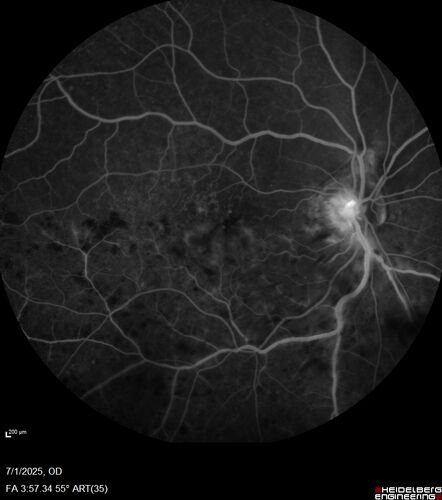

Hemi-CRVO - dual trunk vein

81 year old female mild vision loss - Anatomy shows dual trunk vein with one blocked. About 20 percent of people have this anatomy